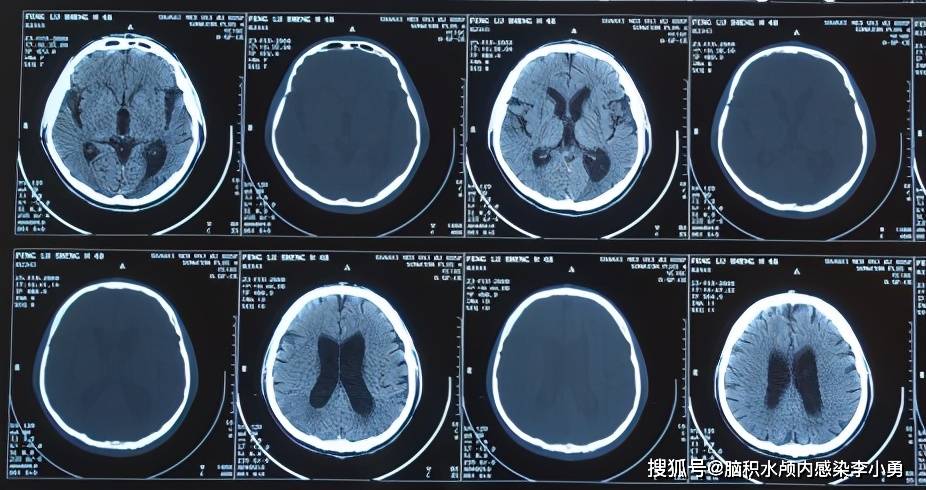

在山西省某三甲医院复查,头颅ct提示"梗阻性脑积水,侧脑室,三脑室增大

2020年8月17日入院治疗54天即2020年8月29日,查头颅ct侧脑室,第四脑室